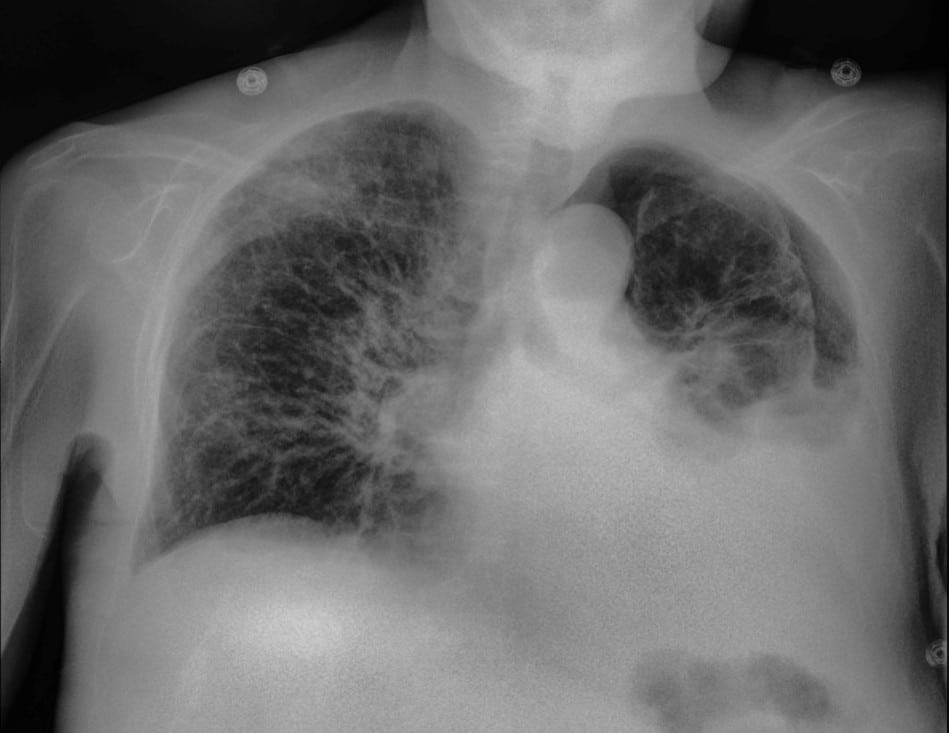

lung disease or infection

more pneumonia cases found compared to X-ray thanks to dual-energy images⁴

Lung Injury and Pulmonary Abnormalities